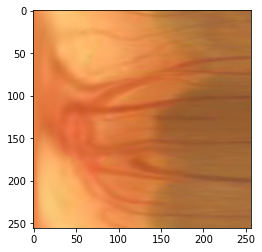

Glaucoma is one of the most severe eye diseases, characterized by rapid progression and leading to irreversible blindness. It is often the case that pathology diagnostics is carried out when the one's sight has already significantly degraded due to the lack of noticeable symptoms at early stage of the disease. Regular glaucoma screenings of the population shall improve early-stage detection, however the desirable frequency of etymological checkups is often not feasible due to excessive load imposed by manual diagnostics on limited number of specialists. Considering the basic methodology to detect glaucoma is to analyze fundus images for the \textit{optic-disc-to-optic-cup ratio}, Machine Learning domain can offer sophisticated tooling for image processing and classification. In our work, we propose an advanced image pre-processing technique combined with an ensemble of deep classification networks. Our \textit{Retinal Auto Detection (RADNet)} model has been successfully tested on Rotterdam EyePACS AIROGS train dataset with AUC of 0.92, and then additionally finetuned and tested on a fraction of RIM-ONE DL dataset with AUC of 0.91.